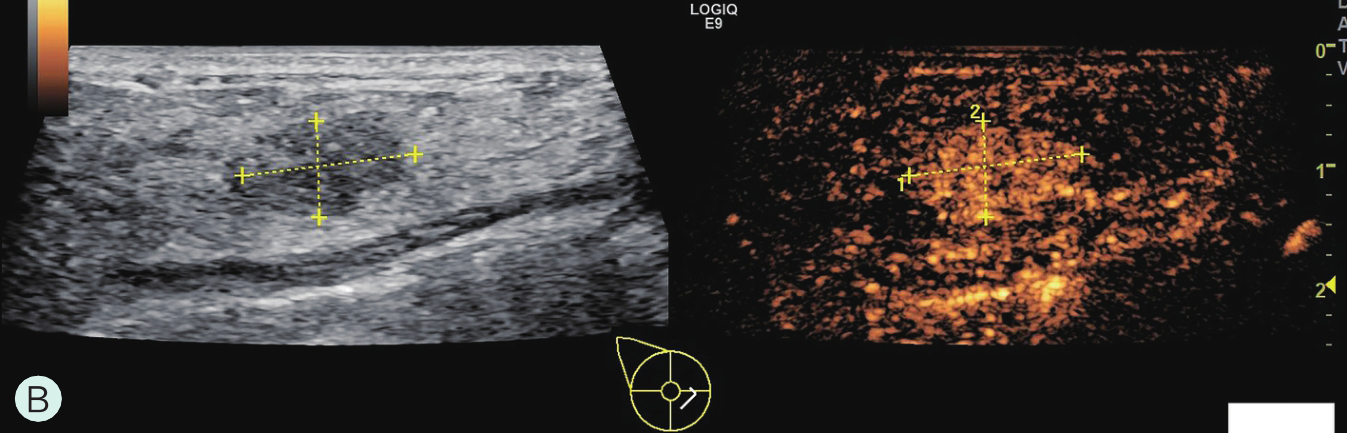

图2-2-1 确定造影病灶

A.病灶二维图像;B、C.病灶CDFI图像;D.同侧腋窝淋巴结情况;E.病灶弹性成像图像